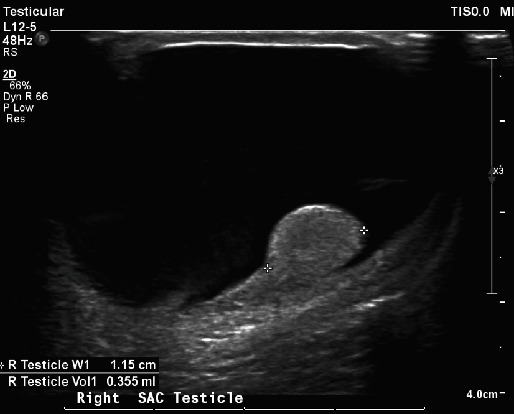

Neonatal testicular torsion (NTT) is a rare but significant condition occurring within the first 30-day postbirth, leading to vascular compromise and potential testicular loss. This paper presents a case of NTT detected incidentally in a neonate with bilateral hydrocele, emphasizing the challenge of early diagnosis and management complexities. The infant underwent surgical intervention involving detorsion and bilateral orchiopexy but eventually required right orchiectomy due to necrosis. The paper highlights the prevalence of NTT in conjunction with hydrocele and stresses the importance of parent education and vigilant follow-up. Various diagnostic methods, primarily ultrasonography, and a range of management strategies are discussed, considering factors such as salvage potential, risk to the contralateral testicle, and surgical intervention's risks and benefits. The paper argues for individualized management, taking into account specific neonate conditions and parental preferences, underlining the essential role of informed and empathetic consultation. The case reinforces the urgent need for increased awareness, early detection, and carefully considered therapeutic approaches to prevent devastating outcomes like infertility and the necessity for lifelong hormone supplementation.

Abstract Image